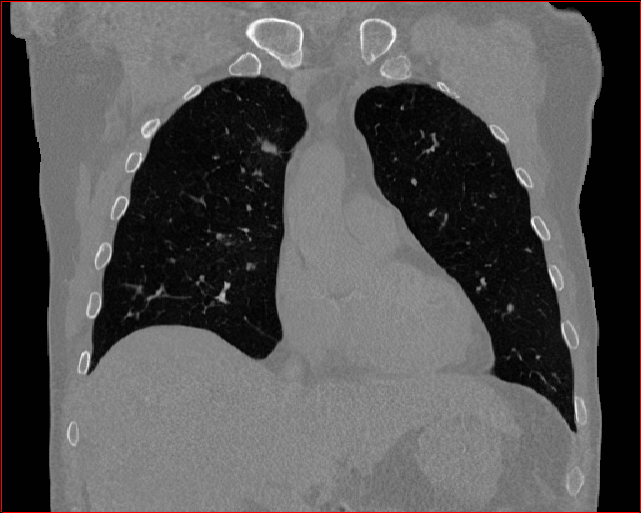

Figure 3 shows the generalizability of MAISI-v2 ControlNet for different body regions and voxel sizes. Figure 4 shows qualitative results for MAISI-v2 ControlNet on 5 types of tumors.

Chest Region

1×1×11\times 1\times 1

mm

384×384×384384\times 384\times 384

Abdomen Region

Figure 3: MAISI-v2 segmentation-guided results for small to large volume size and three different regions.